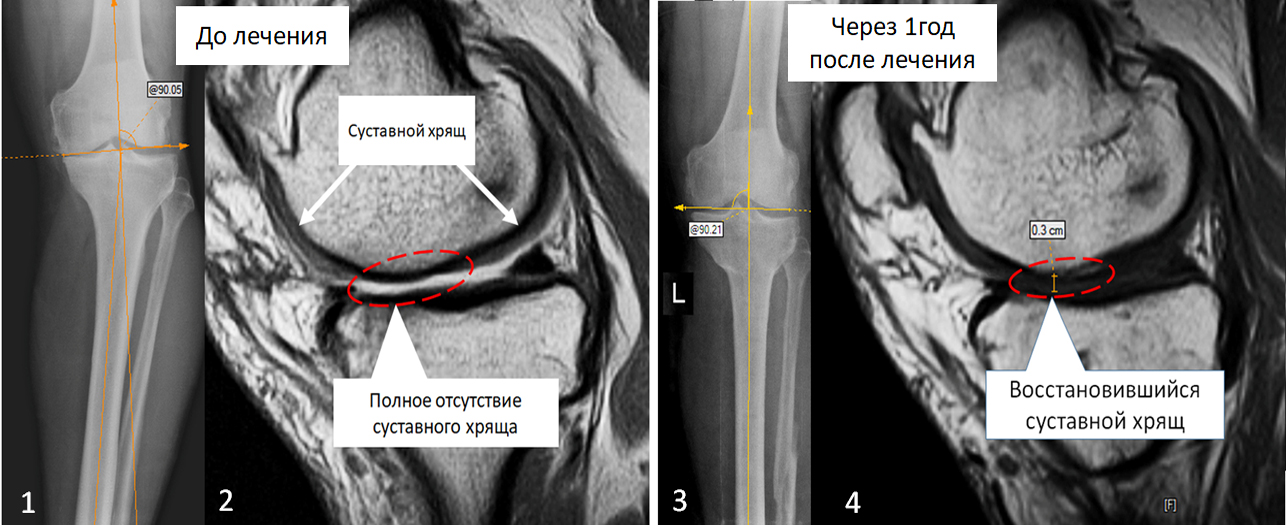

До начала лечения. На рентгенограмме  (снимок 1) - выраженная варусная деформация большеберцовой кости. На МРТ снимках (снимок 2) – имеется участок суставной поверхности с полным отсутствие суставного хряща (обведено пунктирной линией), на месте хряща определяется суставная жидкость. В норме суставной хрящ выглядит как широкая серая полоса (указано стрелками).

Через 1 год после оперативного лечения. На рентгенограмме (снимок 3) - ось большеберцовой кости восстановлена. На МРТ снимках (снимок 4) – на месте отсутствовавшего ранее суставного хряща образовался новый хрящ толщиной до 3 мм (обведено пунктирной линией)